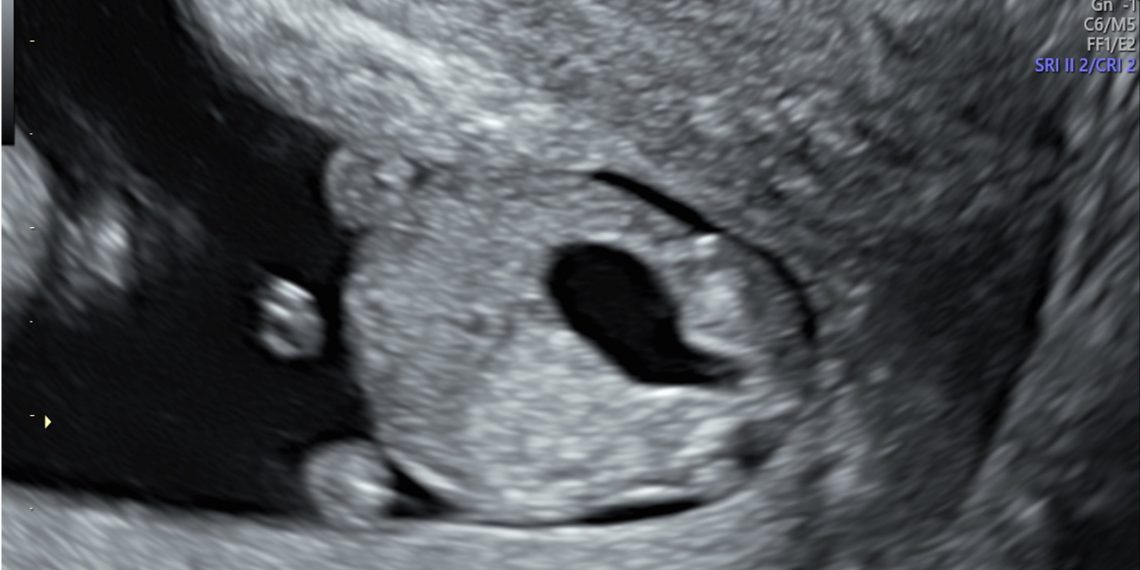

Caso 1 – video

risposta Casodelmese_Luglio20241

Caso 2